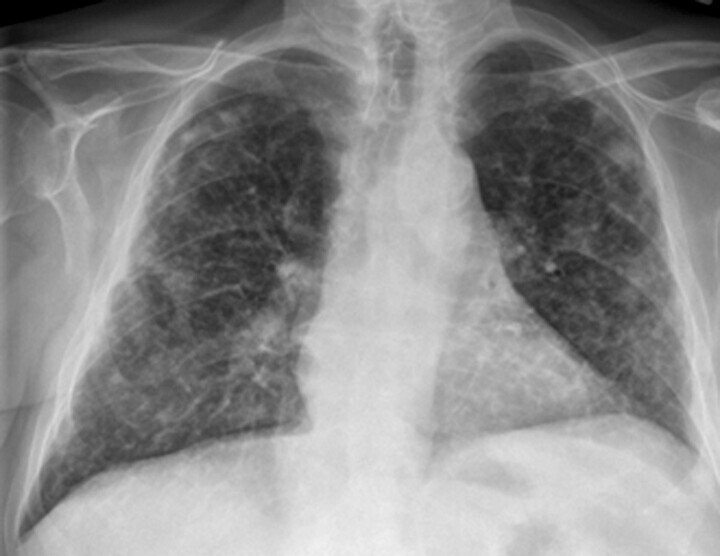

In der Lungenfunktionsanalyse zeigt sich eine restriktive Ventilationsstörung mit kleiner TLC (totale Lungenkapazität) und Behinderung des CO-Transfers (Diffusionsstörung). In Ruhe kann die Blutgasanalyse normal ausfallen, unter leichter Belastung (40 Watt) jedoch entwickelt sich eine Hypoxämie. Das HR-CT kann bereits frühe Stadien der EAA nachweisen (disseminierte Milchglastrübungen, Retikulationen, Fibrose), die in der Röntgen-Thorax-Übersicht oft schwer zu erkennen sind. In der Röntgen-Thorax-Übersicht in 2 Ebenen findet sich eine disseminierte, feinfleckige, manchmal feinretikuläre Zeichnungsvermehrung über allen Lungenabschnitten (Abb. 27.5). Für die Diagnostik ist das HR-CT, wie bei allen interstitiellen Lungenerkrankungen essenziell. Die akute EAA zeigt dabei ein relativ typisches Muster mit großflächigem Milchglas und häufig ein sogenanntes Mosaikmuster. Die chronische EAA zeigt dagegen unterschiedliche radiologische Muster, sodass die Diagnose sich oft schwierig gestaltet.

Abb. 27.5 Röntgen-Thorax-Übersicht bei exogen-allergischer Alveolitis

Disseminierte kleinfleckig-retikuläre Lungenzeichnung.

a Übersichtsaufnahme.

b Detailaufnahme linkes Unter- und Mittelfeld.